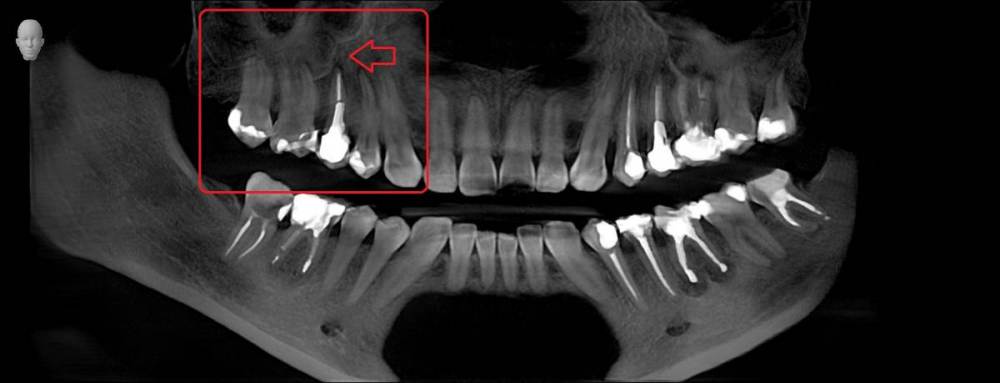

Три месяца назад стала болеть десна верхнего зуба возле коронки (пятый), только с внутренней стороны , но при этом все время языком хотелось трогать соседний зуб( 4). Врач ничего не увидела, сказала полоскать. На давление, холод, постукивания зуб с коронкой и соседние не реагировали. Через какое то время возникло ощущение что 4 верний зуб как будто вырос и немного подвижет, на что врач ответил что я выдумываю, предложил поменять пломбы на соседних зубах, но лучше не стало. Сделала КТ, опять ничего не видят. Ко всему этому добавилась головная боль и усталость. на десне, с внутренней стороны, выше к нёбу между 6 и 7 зубами  выскочила шишка,если сильно нажать то болит, а так нет, выделений нет.  сделали рентген, опять мне говорят, что все ок. На мой вопрос , что это за круги на рентгене, ничего не ответили, к сожалению забыла взять последнюю фото, но на первом прицельном фото этот круг уже виден, на новом больше кругов и они распространились дальше на 6, 7   зубы. На панорамме видно как новооброзование. Погите понять что это?

Прицельное фото в марте  делала, КТ в мае. А новое фото забыла взять.

Panorama.jpg